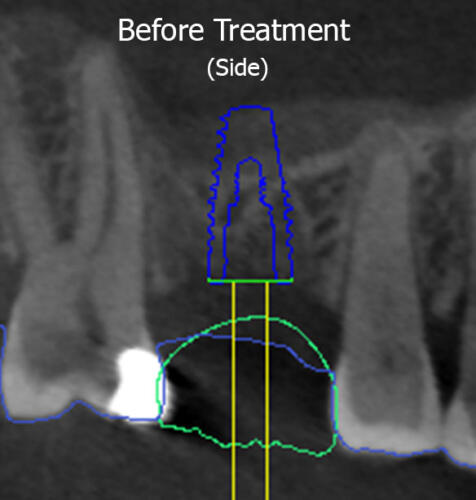

DM had a missing tooth on the top right side and wanted an implant in that area so that he could chew properly again. Planning with digital dentistry found that his sinus had grown in size as a result of the removal of the tooth (as shown by the red dotted line), meaning there was not enough height of jaw bone to support an implant in this area without causing a puncture into the sinus (shown by the transparent overlay of the planned implant site going beyond the red dotted line). As mentioned above, a puncture into the sinus can cause a serious infection with dire consequences.